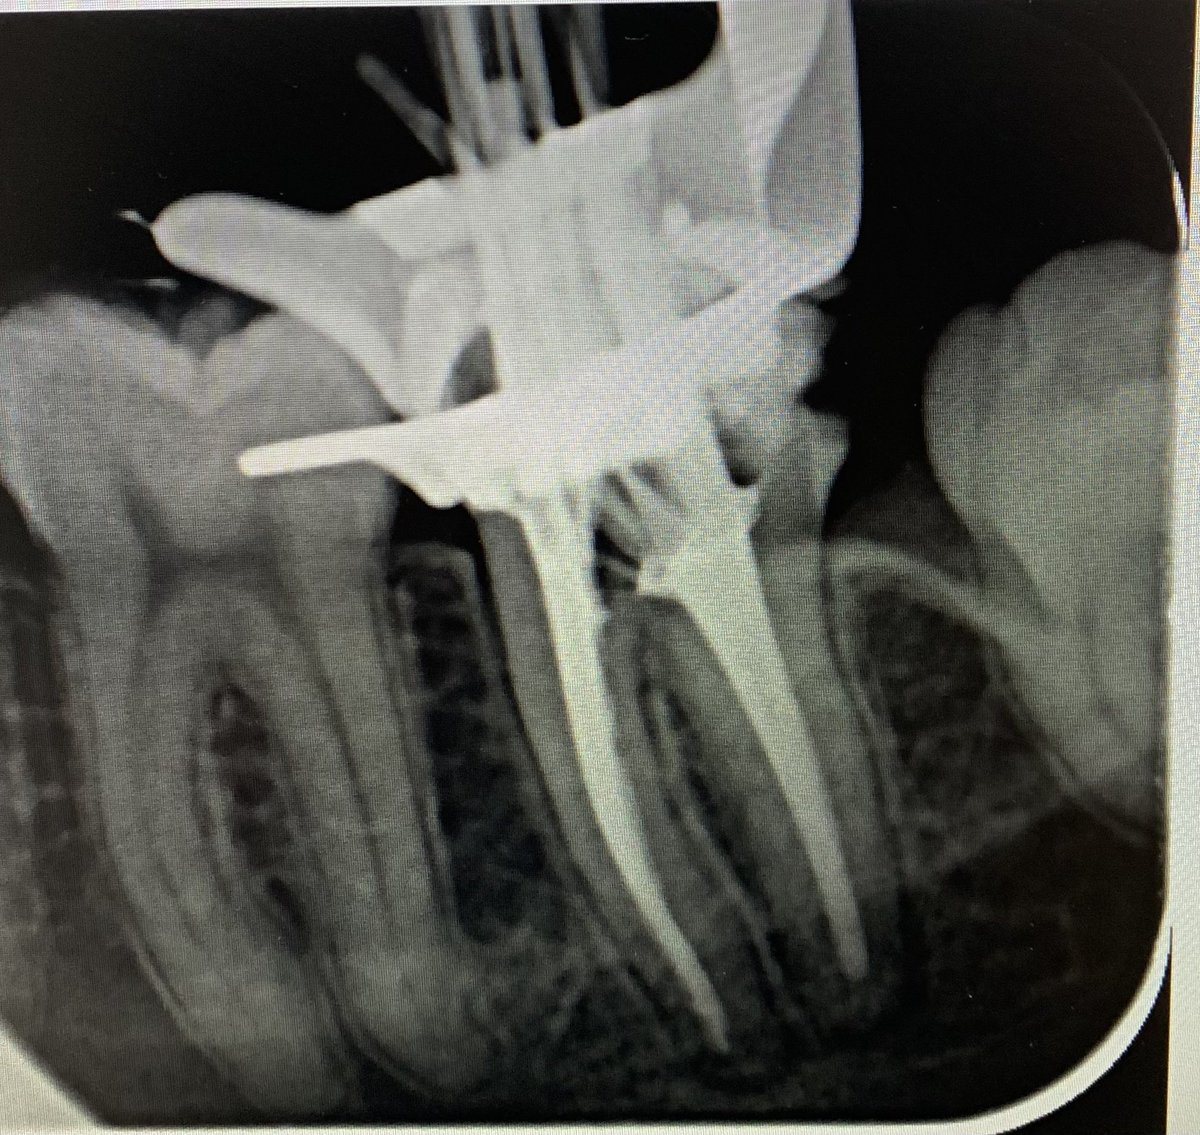

This study explores the diagnostic complexities of rhino-maxillary mucormycosis